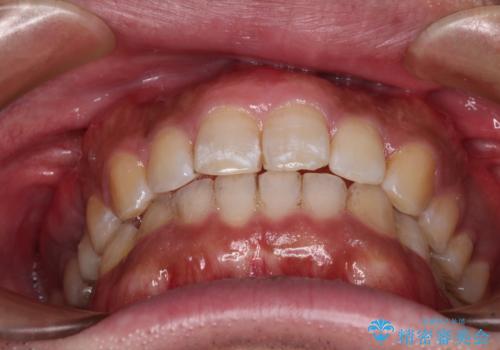

- 上下前歯部の叢生を気にして来院された患者様です。

レントゲン撮影により、右上奥歯が折れていることが分かりました。

患者様自身も何となく違和感を覚えていたとのことで、インプラント補綴治療を行うこととしました。

歯列不正は比較的軽微であったので、インビザラインによる矯正治療とし、矯正治療中にタイミングを見て抜歯とインプラント埋入を行う予定としました。